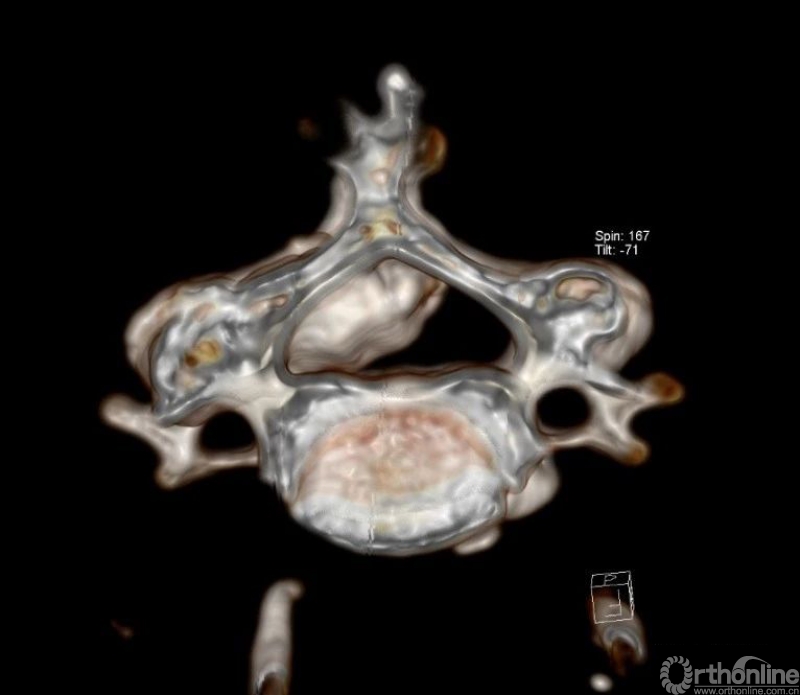

入院查体患者四肢肌张力高,双侧hoffman阳性。CT及MRI检查提示C4/5左侧关节突内缘有一巨大骨块(15mm*16mm),相应节段椎管严重狭窄。椎管内骨块的前端还有一游离骨块。

影像学资料